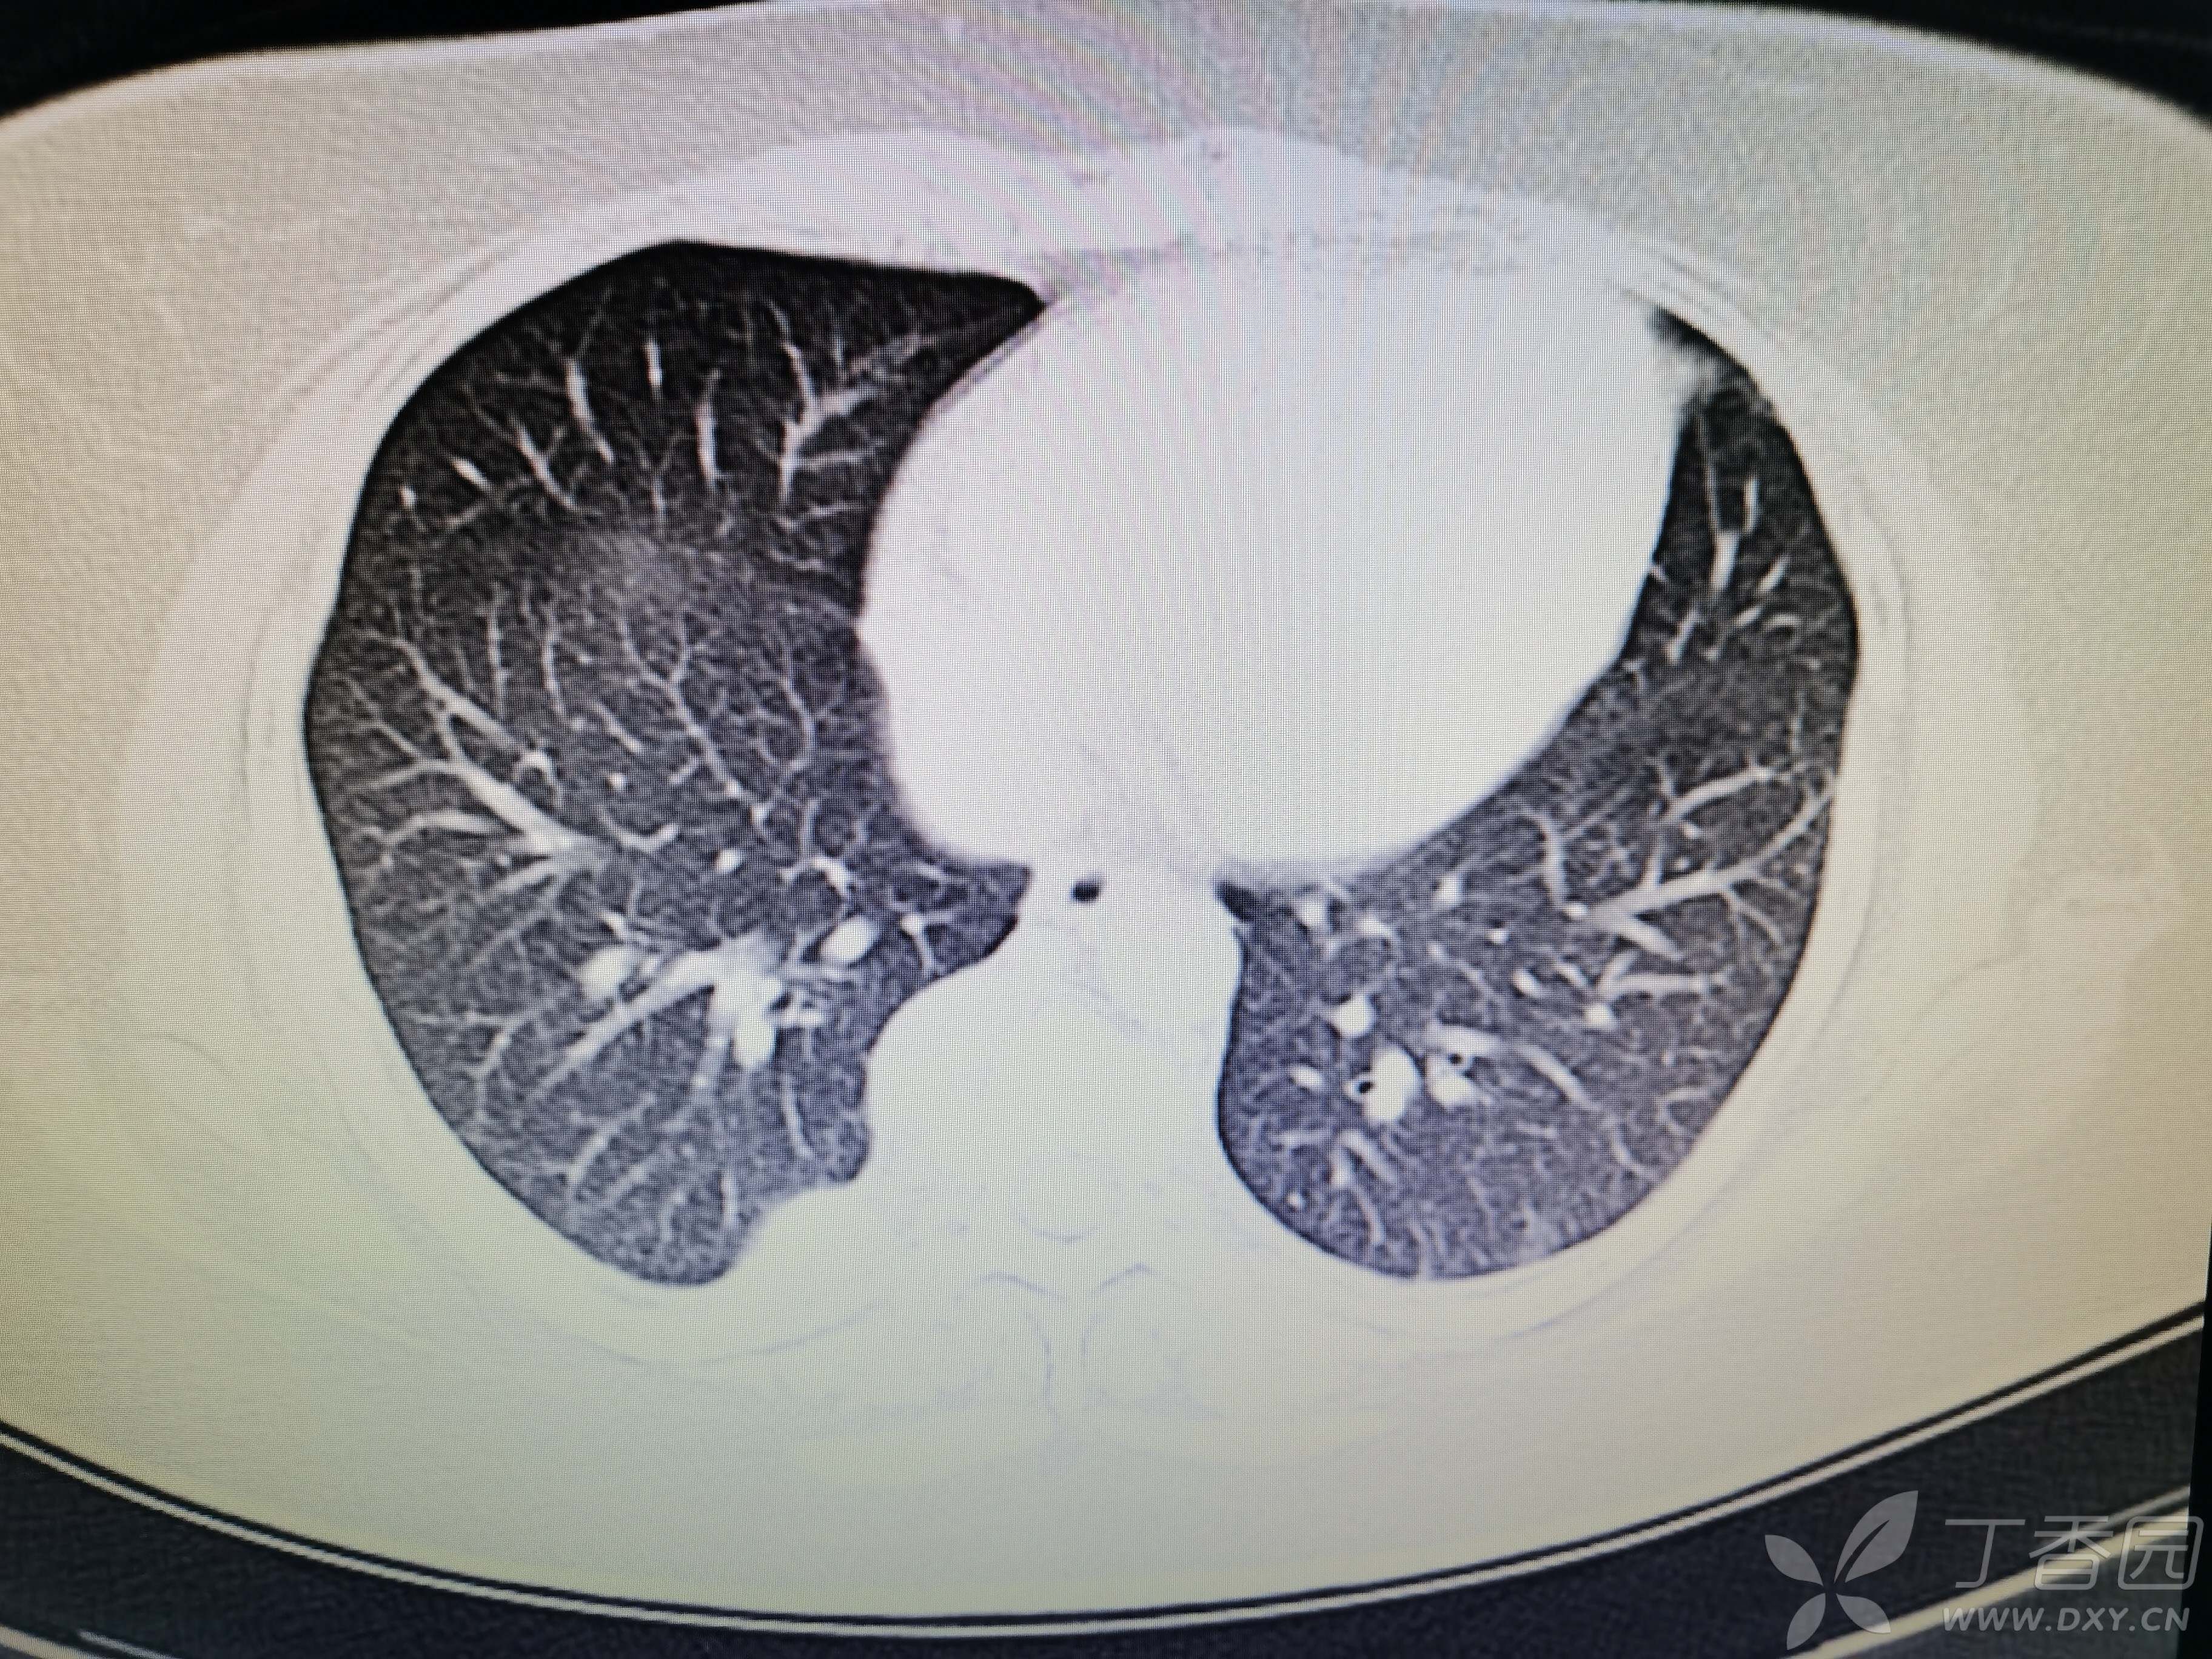

基本信息:女,三十几岁,印度人。。

胸部CT:

如题:猜肺部病灶病理。。